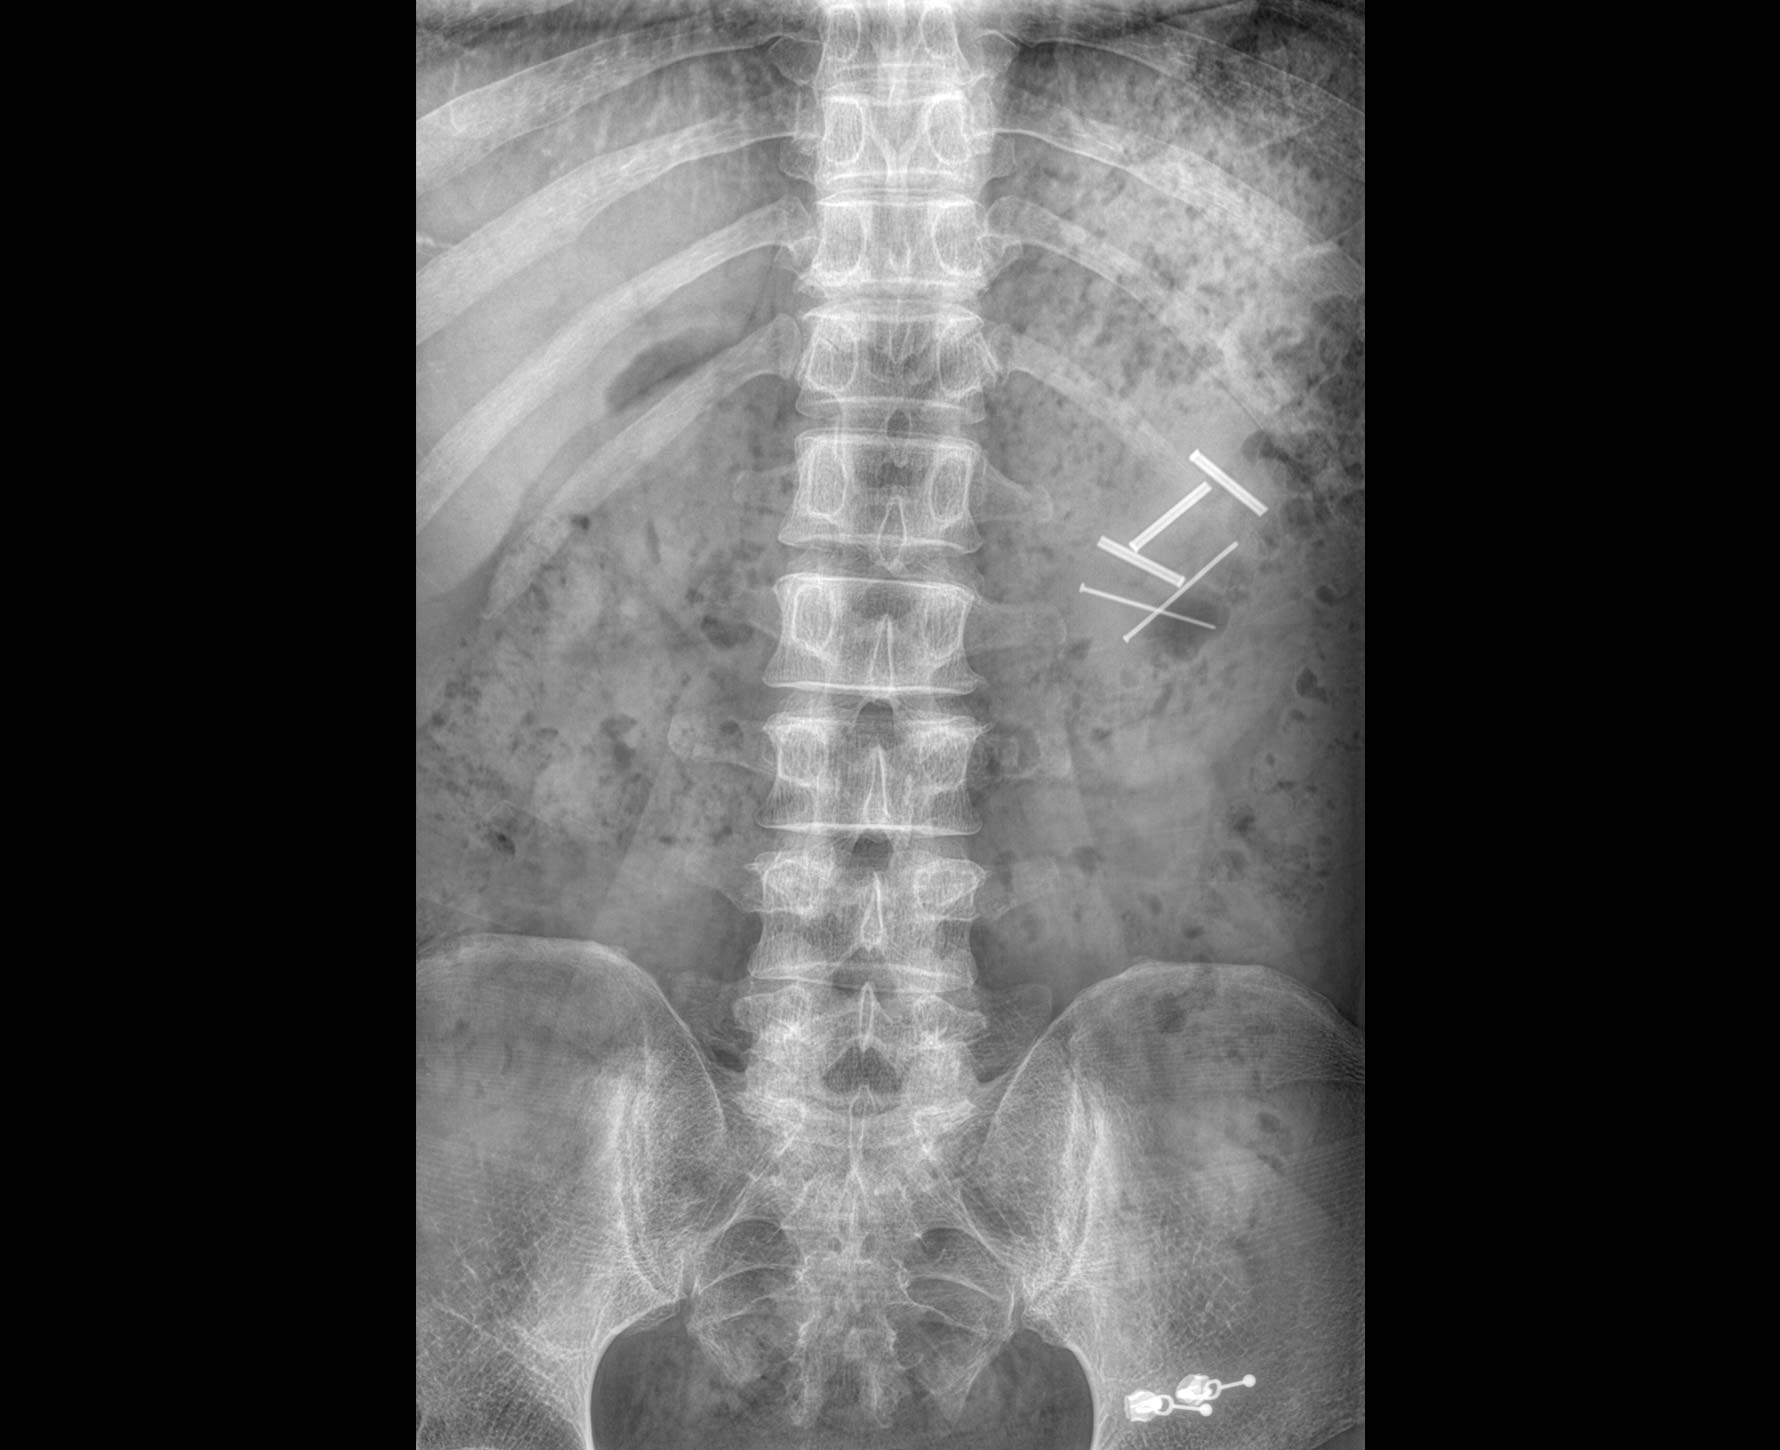

适用于全身各部位摄影

(常规摄影和特殊摄影)

适用于全身各部位摄影

(常规摄影和特殊摄影)